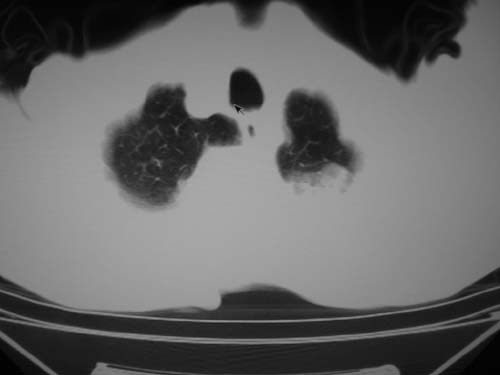

标题: CT19736:男,76岁,咳嗽,胸痛 [打印本页]

标题: CT19736:男,76岁,咳嗽,胸痛

支持左上肺周围型肺癌性并空洞形成伴胸椎转移。

左上沟癌空洞形成并胸椎转移。

考虑癌性空洞并胸椎转移。

空洞内壁有多发结节,支持癌性空洞。

支持左上肺周围型肺癌并空洞形成伴胸椎转移。z左下肺炎

左上肺癌性空洞伴胸椎转移。